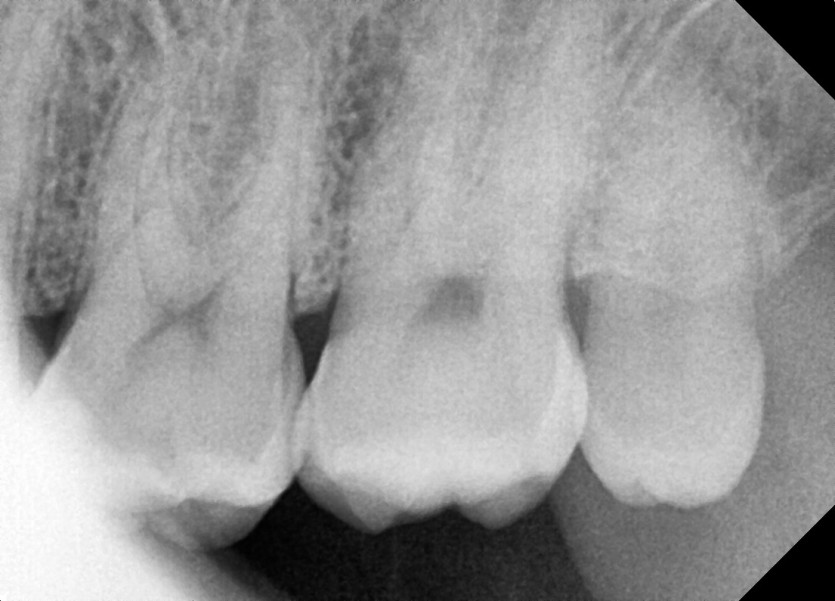

#28,38 사랑니 발치

구강 외과 전문의가 당일 발치했습니다.